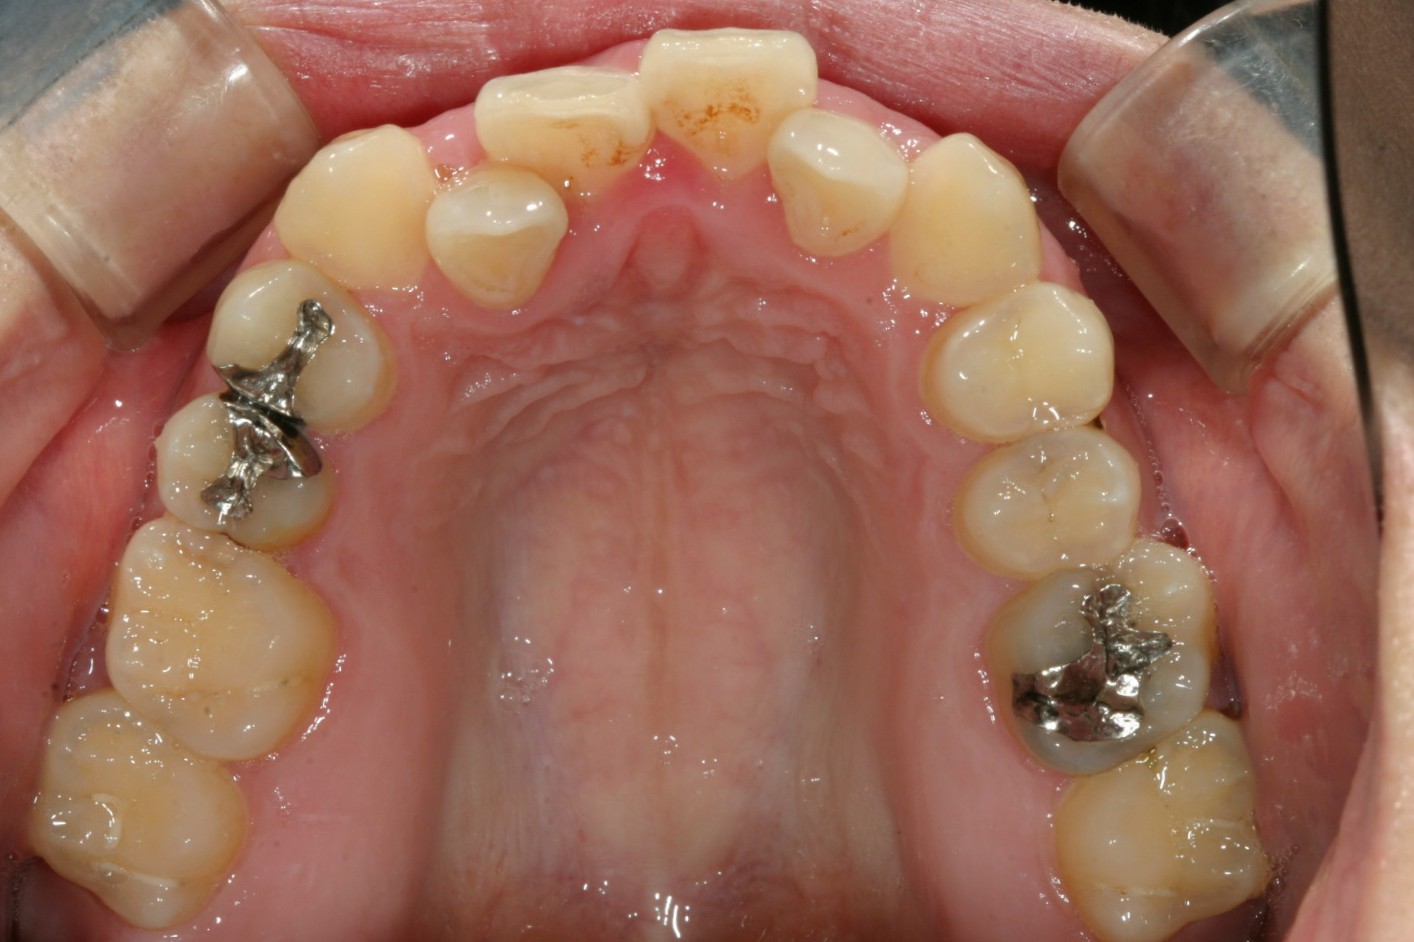

アーチが狭くて前歯が並ぶ隙間が有りません。

下顎もアーチが狭くV字型をしていて叢生が目立ちます。